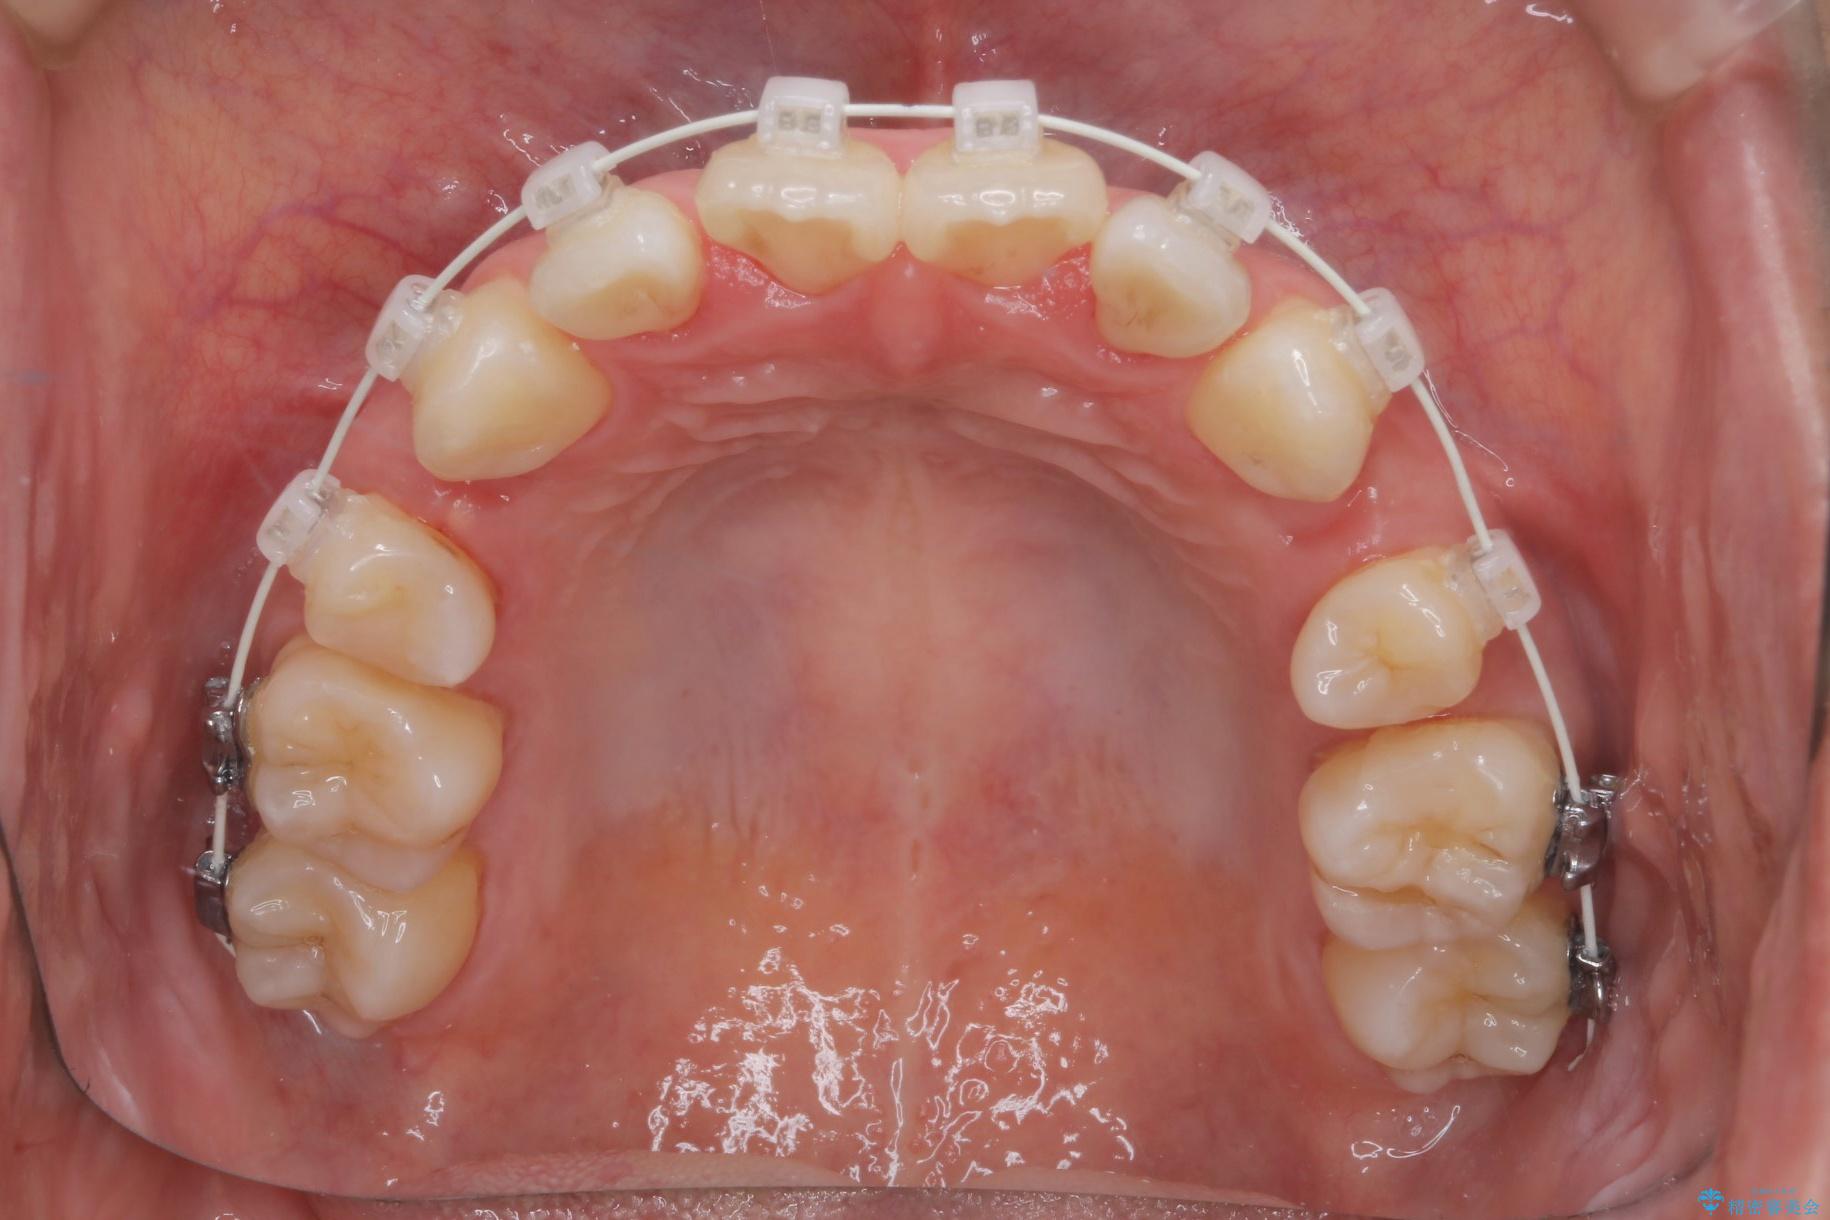

重度の叢生が認められたため、上下左右4番目の歯を抜歯しワイヤー矯正治療を行いました。

- 治療中は違和感や痛みが起こることがあります

- 症状により、抜歯が必要な場合があります

- 治療中は歯磨きがしにくくなるため、虫歯や歯周病になりやすくなります